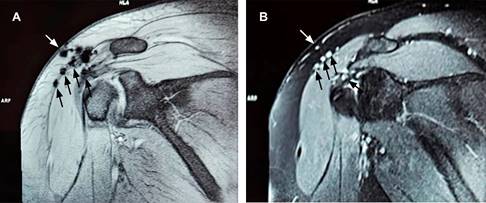

Figura 1: A) Imagen de resonancia magnética de hombro en secuencia gradiente de eco en corte coronal (efecto blooming) mostrando varias señales hipointensas (flechas negras) en borde de músculo deltoides y una en tejido graso (flecha blanca). B) Imagen en secuencia por densidad protónica con supresión grasa, mostrando los mismos elementos, pero con señal hiperintensa (flechas negras y blanca), en paciente postartroscopia de un año de evolución, correspondiendo a artefactos de susceptibilidad magnética.

Los artefactos de susceptibilidad magnética se consideran un tipo de artefacto de desplazamiento químico, en el que la deformidad local del campo magnético origina un registro espacial incorrecto de la señal. Estos artefactos se observan en interfaces entre sustancias con diferentes valores de susceptibilidad, causando distorsión de la imagen, pérdida de señal, áreas focales brillantes y falla en la supresión de grasa. En pacientes con cirugía de hombro o artroscopia previa, las partículas ferromagnéticas finas que se dispersan en el tejido debido a microesquirlas de una broca o de una fresa pueden confundirse con cuerpos sueltos o formación de hueso, así como simular edema o celulitis subcutánea (Figura 1). El artefacto aparece como una señal hiperintensa o alta en algunas secuencias con supresión grasa que dependen del campo principal, es decir, STIR o SPAIR (espectral atenuada con inversión de recuperación). Por lo que es recomendable el uso de secuencias que no dependan de la homogeneidad del campo magnético principal. Pudiendo obtenerse una mejor imagen usando secuencias STIR en lugar de técnicas de saturación de grasa que pueden tener una mayor sensibilidad a la falta de homogeneidad.